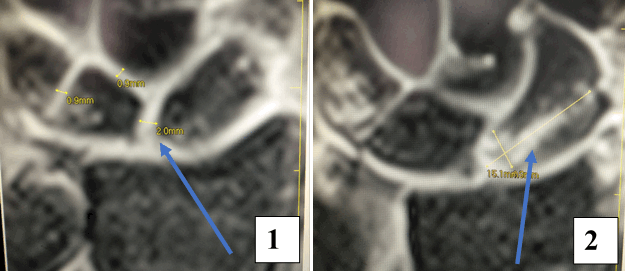

После операции лучезапястный сустав фиксировался иммобилизационной повязкой сроком на 4 недели. По окончанию срока иммобилизации пациентке была рекомендована постепенная разработка лучезапястного сустава, исключающая осевые нагрузки. Через 6 недель с момента операции пациентке было выполнено МРТ исследование для осуществления контроля положения восстановленной связки (рис. 5).

Рис. 5. МРТ исследование правого лучезапястного сустава. На МРТ сканах во фронтальной плоскости: 1) отмечается восстановление пространства между ладьевидной и полулунной костями, отчетливо видна связка; верифицируется биодеградируемый пин и якорный фиксатор в ладьевидной кости; 2) отмечается синовит лучезапястного сустава и отсутствие отека костной ткани ладьевидной кости